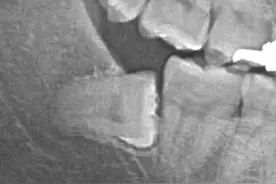

其实一开始是准备到上海市第九人民医院去拔的,因为听说那里的牙科全国第一,后来去了一趟只能工作日去,而且人超多,后来就查了下哪个医院拔牙水平高,最后决定去同济大学附属口腔医院拔,到医院那里的时候已经是十一点二十了,上午已经没办法挂号了,下午吃完饭早早在那儿排队挂号,居然还是第四个,到时间了,先去二楼那边排队,护士问我拍牙片没,我说没有,就去交钱拍了牙片,轮到我时候医生一看,下边牙齿靠近牙神经,拔牙的时候可能因为震动等原因碰到,造成脸部的麻木什么的,说了一通,把我吓得不行,主任建议去做个ct看下,这样可以判断是否影响到拔牙,还能说什么安全第一,立马交钱做ct,主任看完之后确定可以拔,终于可以拔了。